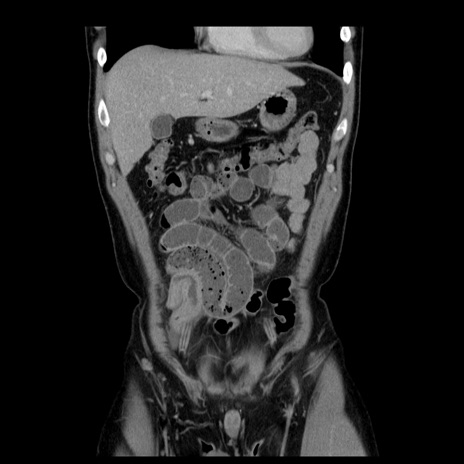

症例4(冠状断像)

【症例】30歳代男性

【主訴】腹痛、嘔吐

【現病歴】昨晩から突然の腹痛あり、その後嘔吐、軟便も出現。腹痛が改善しないため救急搬送となる。2日前にしめ鯖の食事歴あり。

【身体所見】意識清明、苦悶様、BP 135/90mmHg、BT 35.7℃、腹部:平坦、やや硬、心窩部〜臍部に自発痛、圧痛あり、筋性防御+、反跳痛-

【データ】WBC 8100、CRP 0.57